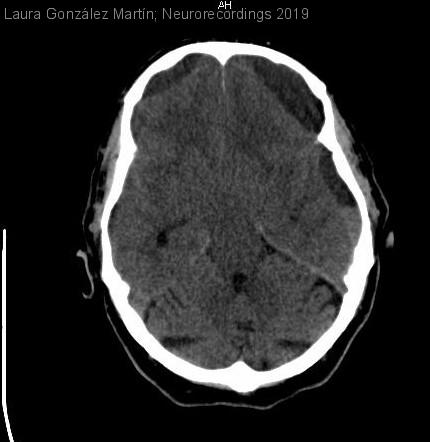

Hematoma subdural bilateral espontáneo con niveles

Hombre | 84 años

Diagnóstico final: Hematoma subdural bilateral espontáneo agudo sobre crónico

Varón de 84 años con deterioro del nivel de conciencia.

Antecedentes personales: hipertenso y diabético; artropatía psoriásica, vitíligo, hiperuricemia, hipertrofia benigna de próstata y pustulosis psoriasiforme.